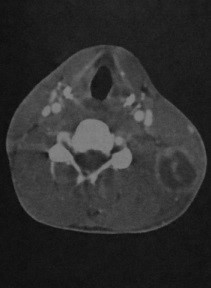

- Диффузная, без четких границ облитерация клетчаточных пространств (флегмона шеи) или одно-/многокамерное скопление жидкости и газа с отеком окружающих тканей и усилением стенки (абсцесс шеи)

- Может содержать серозный экссудат или гной (плотность более 30 HU).

Абсцесс шеи: Объемное образование с воспалительным ободком, накапливающим контраст, может содержать мелкие уровни газ-жидкость.

Флегмона шеи: Участок диффузного повышения плотности и усиления, распространяющийся вдоль фасциальных пространств.

Септический гранулематоз у мужчины 27 лет. КТ с контрастированием: крупный округлый абсцесс с интенсивным усилением стенки, расположенный позади левой грудино-ключично-сосцевидной мышцы. Плотность в полости абсцесса снижена, выявляются перегородки.

КТ с контрастированием: занижнечелюстной абсцесс на уровне угла нижней челюсти слева с множественными внутренними перегородками. Наблюдается характерное снижение плотности в центре абсцесса (жидкость) и усиление стенок. Отек тканей, окружающих абсцесс.